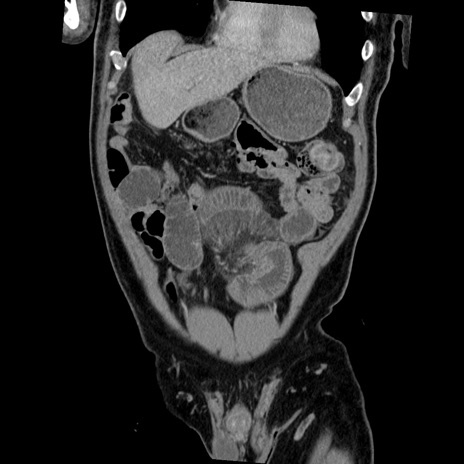

症例22(冠状断像)

【症例】50歳代男性

【主訴】腹痛

【現病歴】AVMからの被殻出血のため回復期リハ病棟入院中。 本日午後3時頃急に下腹部痛が出現した。

【既往歴】AVM、被殻出血、虫垂炎、高血圧

【身体所見】意識晴明、左半身不全麻痺、会話の理解は良好、36.5°C、腹部:膨隆、全体に板状硬、下腹部正中に圧痛点あり、反跳痛-、筋性防御不明、右下腹部にope scar

【データ】WBC 9400、CRP 0.06